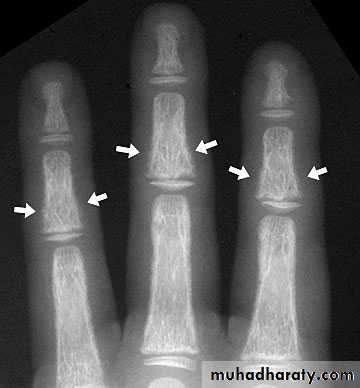

In rickets the changes are maximal where bone growth is occurring , so they are best seen at the knee, wrist and ankle .seen as

. Deficient the zone of provisional calcification .

.widening with irregularly mineralized metaphyses with cupping

.increase distance between the visible epiphysis & the calcified portion of the metaphysis .

.generalized decrease in bone density .

. Deformities of the bones occur because the under mineralized bone is soft , green stick fractures are common .